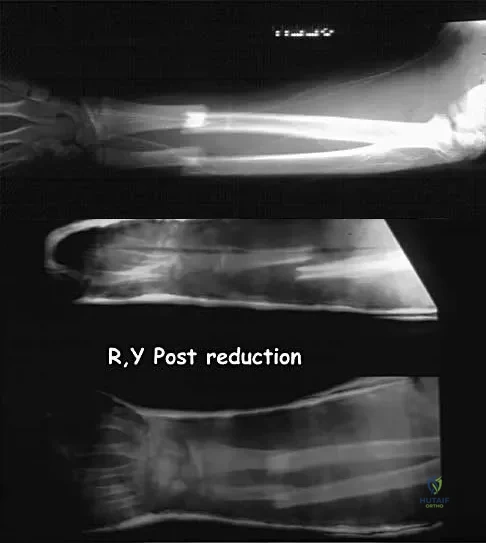

Question 58

Figure 13a shows the radiograph of a 9-year-old girl who sustained complete transverse fractures of the radial and ulnar shafts while in-line skating. A manipulative closed reduction is performed, and the result is seen in Figure 13b. What is the next most appropriate step in management?

Explanation